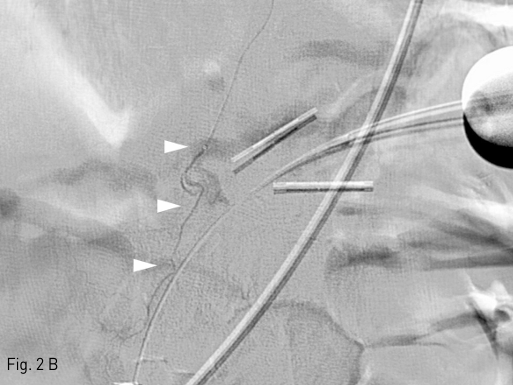

Fig 2B

After further selection of the bleeding branch with a microcatheter (B, arrowheads), embolization was performed with 1:2 mixture of n-butyl-cyanoacrylate (NBCA) and ethiodized oil.